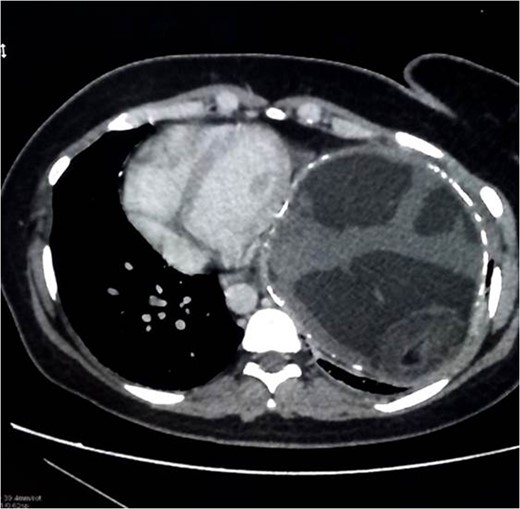

Chest x-ray showed well-defined huge opacity of most left hemithorax with a shift of mediastinum to the right (Fig. 1). CT chest/abdomen/pelvis with IV contrast revealed 20 × 15 × 18 cm3 well-defined mixed cystic lesion within the left lung containing multiple parts of the heterogeneous density with soft tissue elements and fat content. It also showed spots of wall calcification, where the lesion probably originated from the mediastinum, involving most of the left hemithorax. The mass compressed the mediastinal structures, great vessels, and airways (Fig. 2). It is surrounded by a consolidation collapsed with a marked shift of mediastinum to the right side (Figs 2 and 3). No mediastinal lymphadenopathy and the right lung was clear. The spleen was enlarged with multiple cysts that varied in size with no significant enhancement post IV contrast in arterial and portal phases (Figs 2 and 4). The liver was unremarkable. Hematological tests were within normal limits. Mantoux test and Sputum culture were negative.